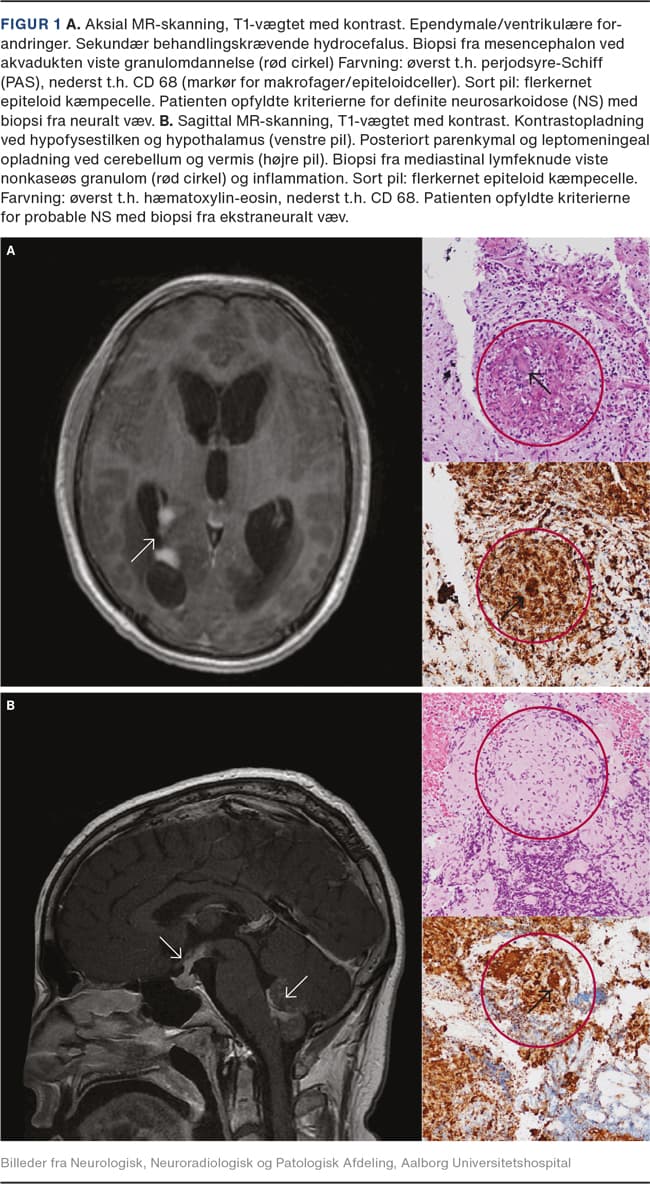

Diffus inflammation og noduli i leptomeninges er en hyppigt set tilstand og viser sig klinisk som subakut lymfocytær meningitis med hovedpine og rammer især de basale meninges [4-6], men kan være placeret over konveksiteterne. Komplikationer er ventrikulitis, hydrocefalus, evt. med livstruende forhøjet intrakranielt tryk (Figur 1A) eller kranienerveudfald.

Sarkoid inflammation og granulomer i hjernen kan give en række neurologiske problemer afhængigt af udviklingshastighed, lokalisation og omfanget af den inflammatoriske proces. Ved NS ses der ofte påvirkning af hypofysen og hypothalamus [7, 9-11] (Figur 1B), hvilket kan give neuroendokrine forstyrrelser som hypofyseinsufficens og chiasmainvolvering med synsudfald eller hypotalamiske symptomer med træthed, tørst, apati og ændret temperaturregulering. NS i andre dele af hjernen kan bl.a. give epileptiske anfald, hemiparese, afasi eller ataksi afhængigt af inflammationens placering [5, 7, 9]. Spredte periventrikulære og subkortikale white matter lesions (WM-læsioner), som giver mere diffuse symptomer, ses. Vaskulære forandringer, som er udløst af vaskulitis, eller inflammatorisk tryk på arterier eller hjernens drænvener, kan give et strokelignende billede [12].

Ved NS anvendes MR-skanning med gadoliumkontrast [10, 16]. Inflammation ses som øget kontrastoptagelse bedst på T1-vægtede sekvenser (Figur 1og Figur 2). MR-skanningsfund, der rejser særlig mistanke om NS er: inflammatoriske forandringer ved kranienerver, i leptomeninges, i hjernevævet især omkring hypofysen/hypothalamus eller tumorlignende granulomer (Figur 2A), evt. med masseeffekt. Diffus og/eller nodulær leptomeningeal opladning er typisk, især i basale meninges og kan give involvering af kranienerver eller hydrocefalus. Periventrikulære eller subkortikale WM-læsioner er hyppige. I medulla er leptomeningeal opladning og/eller granulomer, oftest lokaliseret torakalt evt. som en langstrakt læsion over 2-3 segmenter typisk [13].